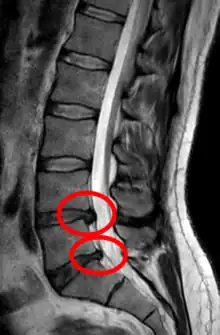

- Magnetic resonance imaging is the gold standard study for confirming a suspected LDH. With a diagnostic accuracy of 97%, it is the most sensitive study to visualize a herniated disc due to its significant ability in soft tissue visualization. MRI also has higher inter-observer reliability than other imaging modalities. It suggests disc herniation when it shows an increased T2-weighted signal at the posterior 10% of the disc. Degenerative disc diseases have shown a correlation with Modic type 1 changes. When evaluating for postoperative lumbar radiculopathies, the recommendation is that the MRI is performed with contrast unless otherwise contraindicated. MRI is more effective than CT in distinguishing inflammatory, malignant, or inflammatory etiologies of LDH. It is indicated relatively early in the course of evaluation (<8 weeks) when the patient presents with relative indications like significant pain, neurological motor deficits, and cauda equina syndrome. Diffusion tensor imaging is a type of MRI sequence used for detecting microstructural changes in the nerve root. It may be beneficial in understanding the changes that occur after herniated lumbar disc compresses a nerve root, and might help in differentiating the patients that need surgical intervention. In patients with a high suspicion of radiculopathy due to lumbar disc herniation, yet the MRI is equivocal or negative, nerve conduction studies are indicated.[44] T2-weighted images allow for clear visualization of protruded disc material in the spinal canal.

MRI scan of large herniation (on the right) of the disc between L4 and L5 vertebrae

A rather severe herniation of the L4–L5 disc

Example of a herniated disc at L5–S1 in the lumbar spine